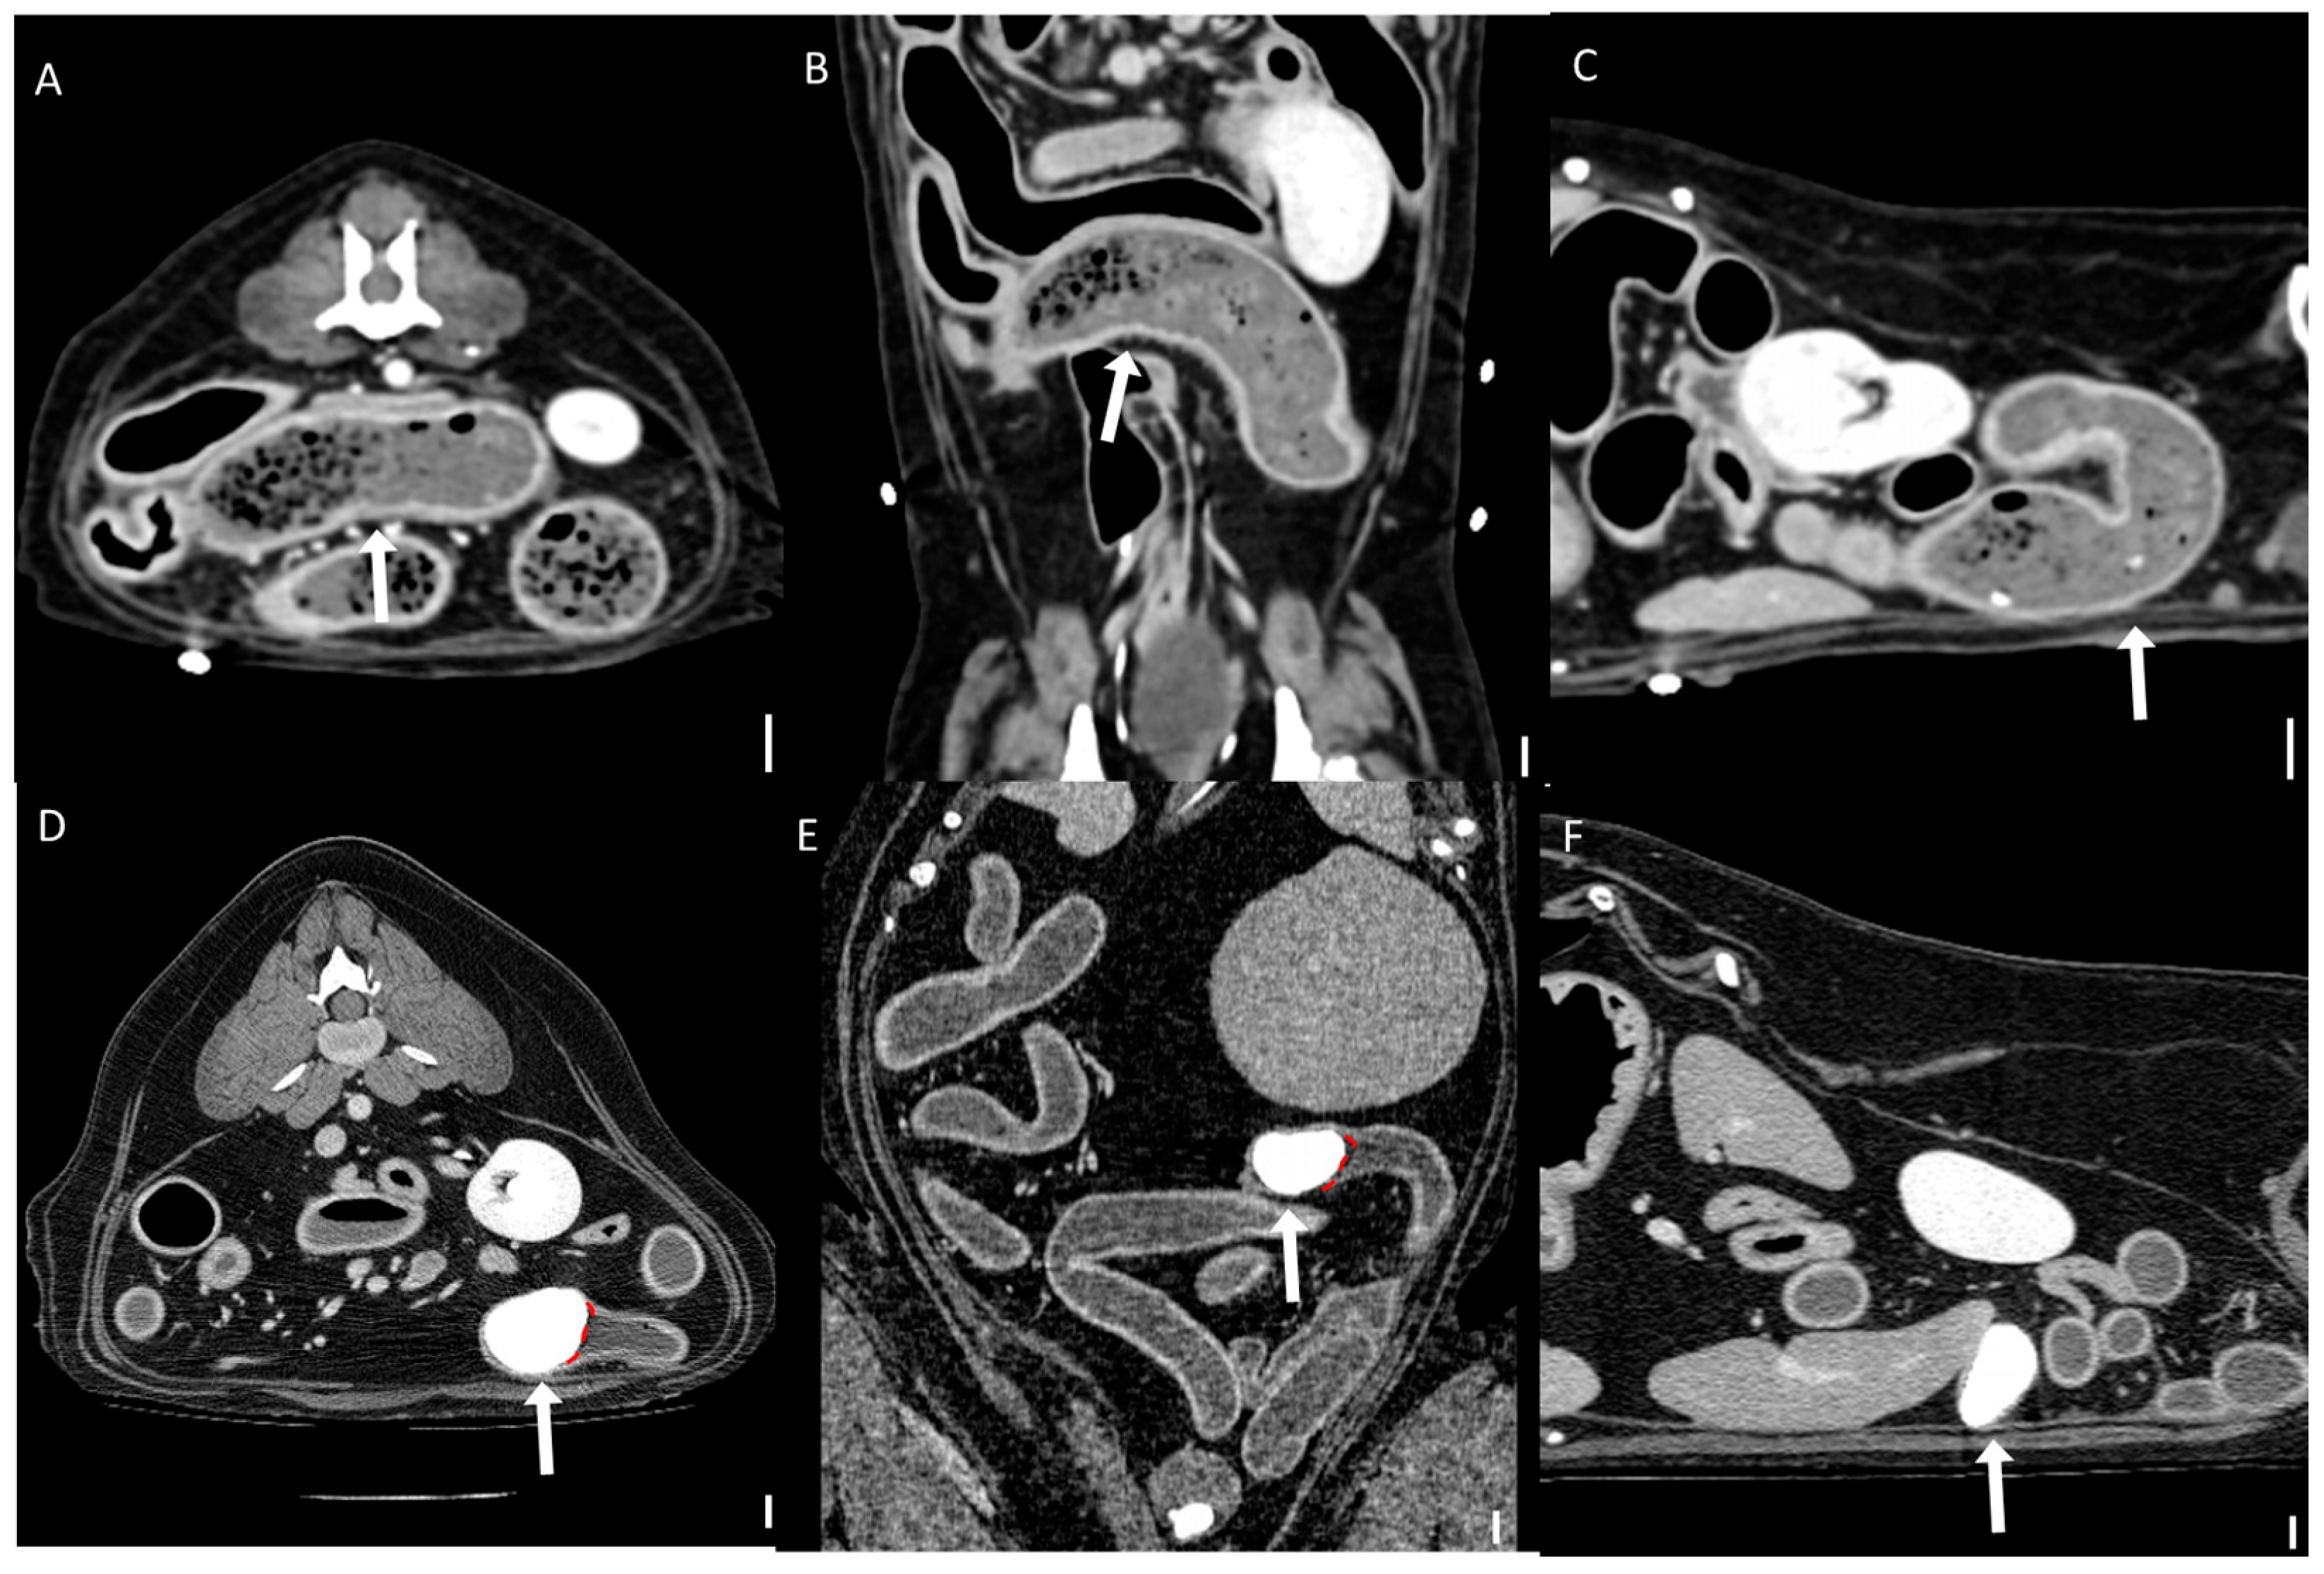

Figure 7. Representative CT images of the boundary between foreign bodies and intestinal contents (scale bar equals 1 cm). (AC) Multiplanar CT images showing an unclear boundary between a foreign body and the surrounding intestinal contents: (A) transverse, (B) dorsal, and (C) sagittal views. The obstruction was caused by a bezoar (arrows) identified as memory foam. (DF) Multiplanar CT images showing a clear boundary (dashed line) between the foreign body and the surrounding intestinal contents: (D) transverse, (E) dorsal, and (F) sagittal views. The obstruction was caused by a stone (arrows).

The qualitative CT findings are summarized in Table 3 and Table 4. A transition zone was observed in 92.3% (12/13) of bezoar cases and 41.7% (5/12) of distinct foreign body cases (p = 0.011). Cases with gastric foreign bodies were excluded from this analysis due to the ambiguity of transition zone identification in the stomach. Clear boundaries between the foreign body and intestinal contents were significantly more common in the distinct foreign body group (94.4%, 17/18) than in the bezoar group (33.3%, 5/15) (p < 0.001; Figure 7). There was no significant difference in the anatomical location of foreign bodies between the groups (p = 0.625), with the jejunum being the most frequently affected segment in both (46.7% of bezoars and 38.9% of distinct foreign bodies).